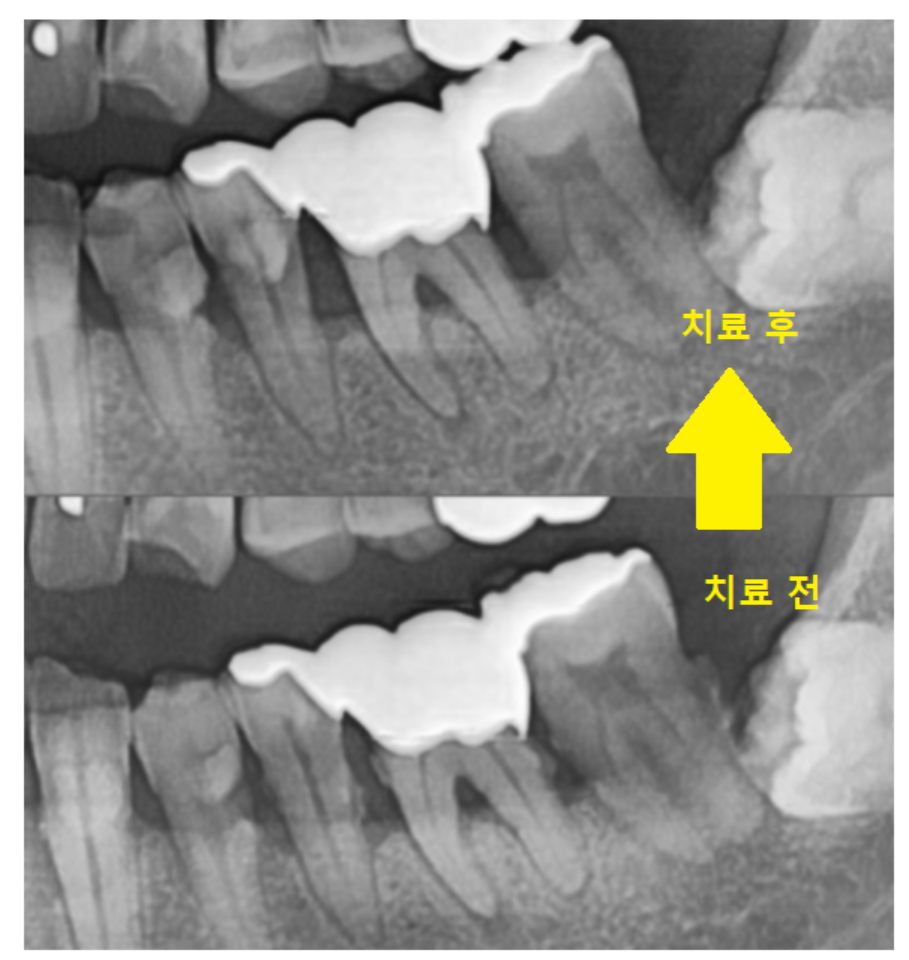

원인을 파악하여 재신경치료나, 잇몸 치료 등이 동반될 수 있습니다.

염증 상태를 오래 방치하면 염증이 뼈를 녹이고,

치아를 살리기 어려워질 수 있습니다.

염증 초기라면 간단한 약 처방으로 호전될 수 있지만,

진행된 경우라면 적극적인 치료가 필요합니다.

특히 잇몸뼈 손상이 심한 경우,

잇몸 치료는 필수!!